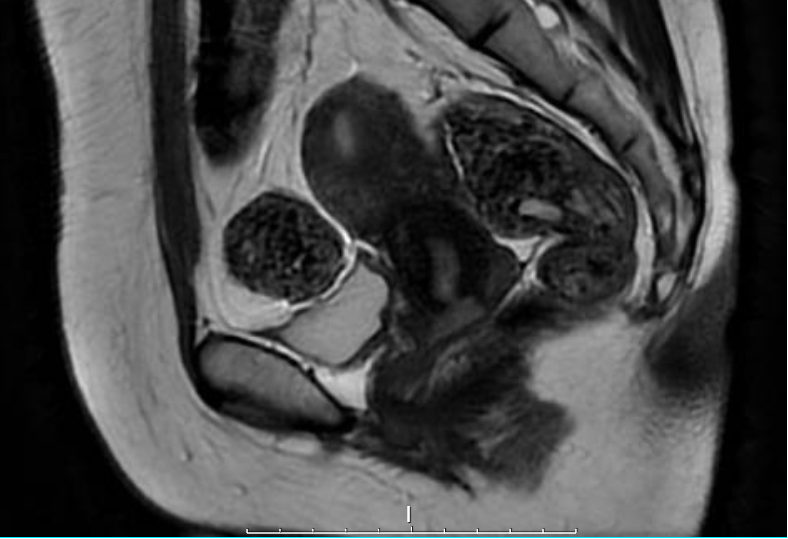

3月30日,田女士接受了腹腔镜广泛宫颈切除术 + 前哨淋巴结切除术。

精准切除病灶:切除宫颈病变组织,完整保留子宫体;

微创技术:腹腔镜切口小、恢复快,减少对盆腔的损伤;

前哨淋巴结评估:术中快速检测淋巴结(双侧共5枚)均未发现转移,为保宫提供了重要依据!

✔ 宫颈切除标本显示肿瘤仅浸润至宫颈壁内 1/3,切缘距离肿瘤边缘处最近仍有1.8cm;

✔ 无脉管癌栓、无神经侵犯,免疫组化提示 HPV 相关型黏液腺癌;

✔ 激素受体(ER/PR)弱阳性,增殖指数(Ki-67)70% 提示需密切随访。

根据2025NCCN指南,田女士5年生存预期达85%,术后2年可尝试自然受孕。目前她正接受个体化随访方案。